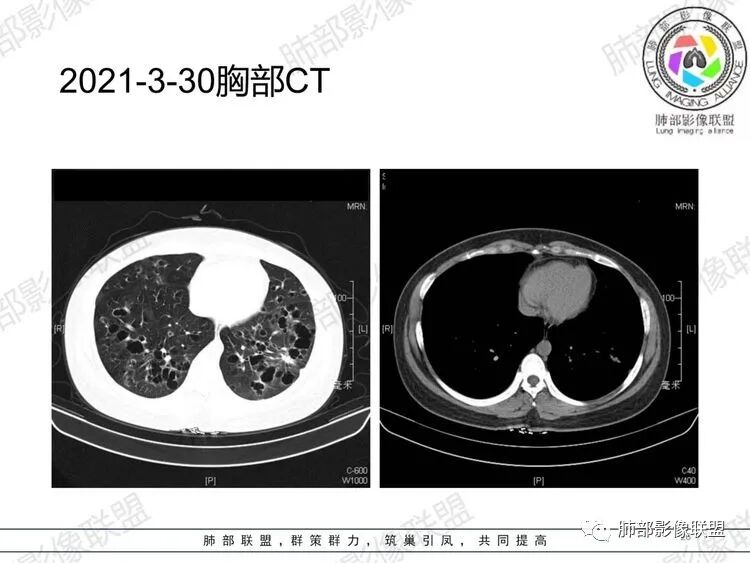

【每日晨读】年轻女性,双肺弥漫奇异囊腔

晨读:双肺多发大小不等囊腔影,部分囊有融合,形态不规则,部分壁偏薄,部分囊壁偏厚,囊壁可见结节?血管?右肺上叶及左肺下叶可见条状高密度影,双侧胸膜结节样增厚,临床年轻女性,考虑LAM,鉴别LIP

晨读:女,31,间断咳嗽咳痰9个月,双肺多发大小不等囊泡影,壁薄厚不均,部分囊泡融合成片,双肺另见结节影,边界清晰,考虑PLCH,LAM。

晨读,青年女性,双肺及胸膜下多发大小不等囊腔,大部分呈薄壁,部分囊壁略厚,边缘毛糙,部分囊腔有融合,双肺内散在条状高密度影,考虑LAM

晨读:女,31,间断咳嗽、咳痰9月。卵巢交界性囊腺瘤术后。胸部CT:双肺多发大小不等薄壁囊腔影,部分融合,形态不规则,个别囊壁偏厚。右肺上叶及左肺下叶纤维索条影。左下叶不规则囊腔影,壁不均匀增厚,周围不规则实性成分加GGO,放射性毛刺,胸膜牵拉。考虑:囊腔型Ca?转移?鉴别PLCH,Lam,LIp,BHD,CF,CPAM等,听大咖解析。

胸部CT:两肺多发囊腔,中上肺受累为主,囊腔形态不规则(囊有点丑),分叶状,囊壁厚薄不均,大部分囊壁薄。尚有一些结节影。